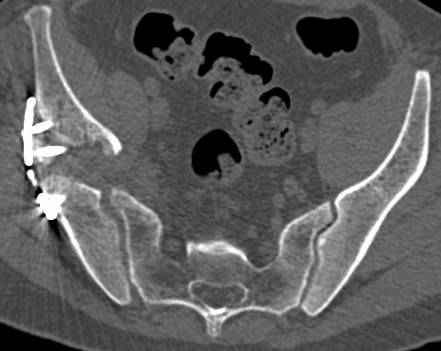

высылаю дополнительно сканы.

По отдельным срезам и тем более по реконструкции трудно судить о сращении крыла и задней колонны с осевым скелетом.

В большинстве случаев при двухколонных переломах

в итоге получается прочный бублик с дыркой. При эндопротезировании в дырку помещается головка, а чашка должна неплохо заклиниться в бублике.

Главное, чтобы бублик не был разорван, что не очень понятно на представленных снимках.

Поэтому хотелось бы дообследовать больного (разумеется включив стандартные проеции judet,и срезы показывающие сращение)

Хорошо бы на рентгенограммы взглянуть и побольше срезов по своду. С каким отломком головка контактирует и как ее состояние.

Дополнительные сканы

сканы.jpg